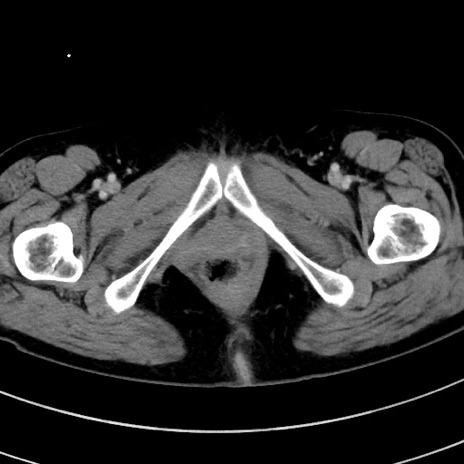

症例9(横断像)

【症例】 60歳代女性

【主訴】むかつき、みぞおちの痛み

【現病歴】3日前よりむかつきがあり、食事がとれない。

【既往歴】糖尿病

【身体所見】発熱なし、心窩部圧痛軽度あるも、腹膜刺激症状なし。

【データ】WBC 7400、CRP 1.92